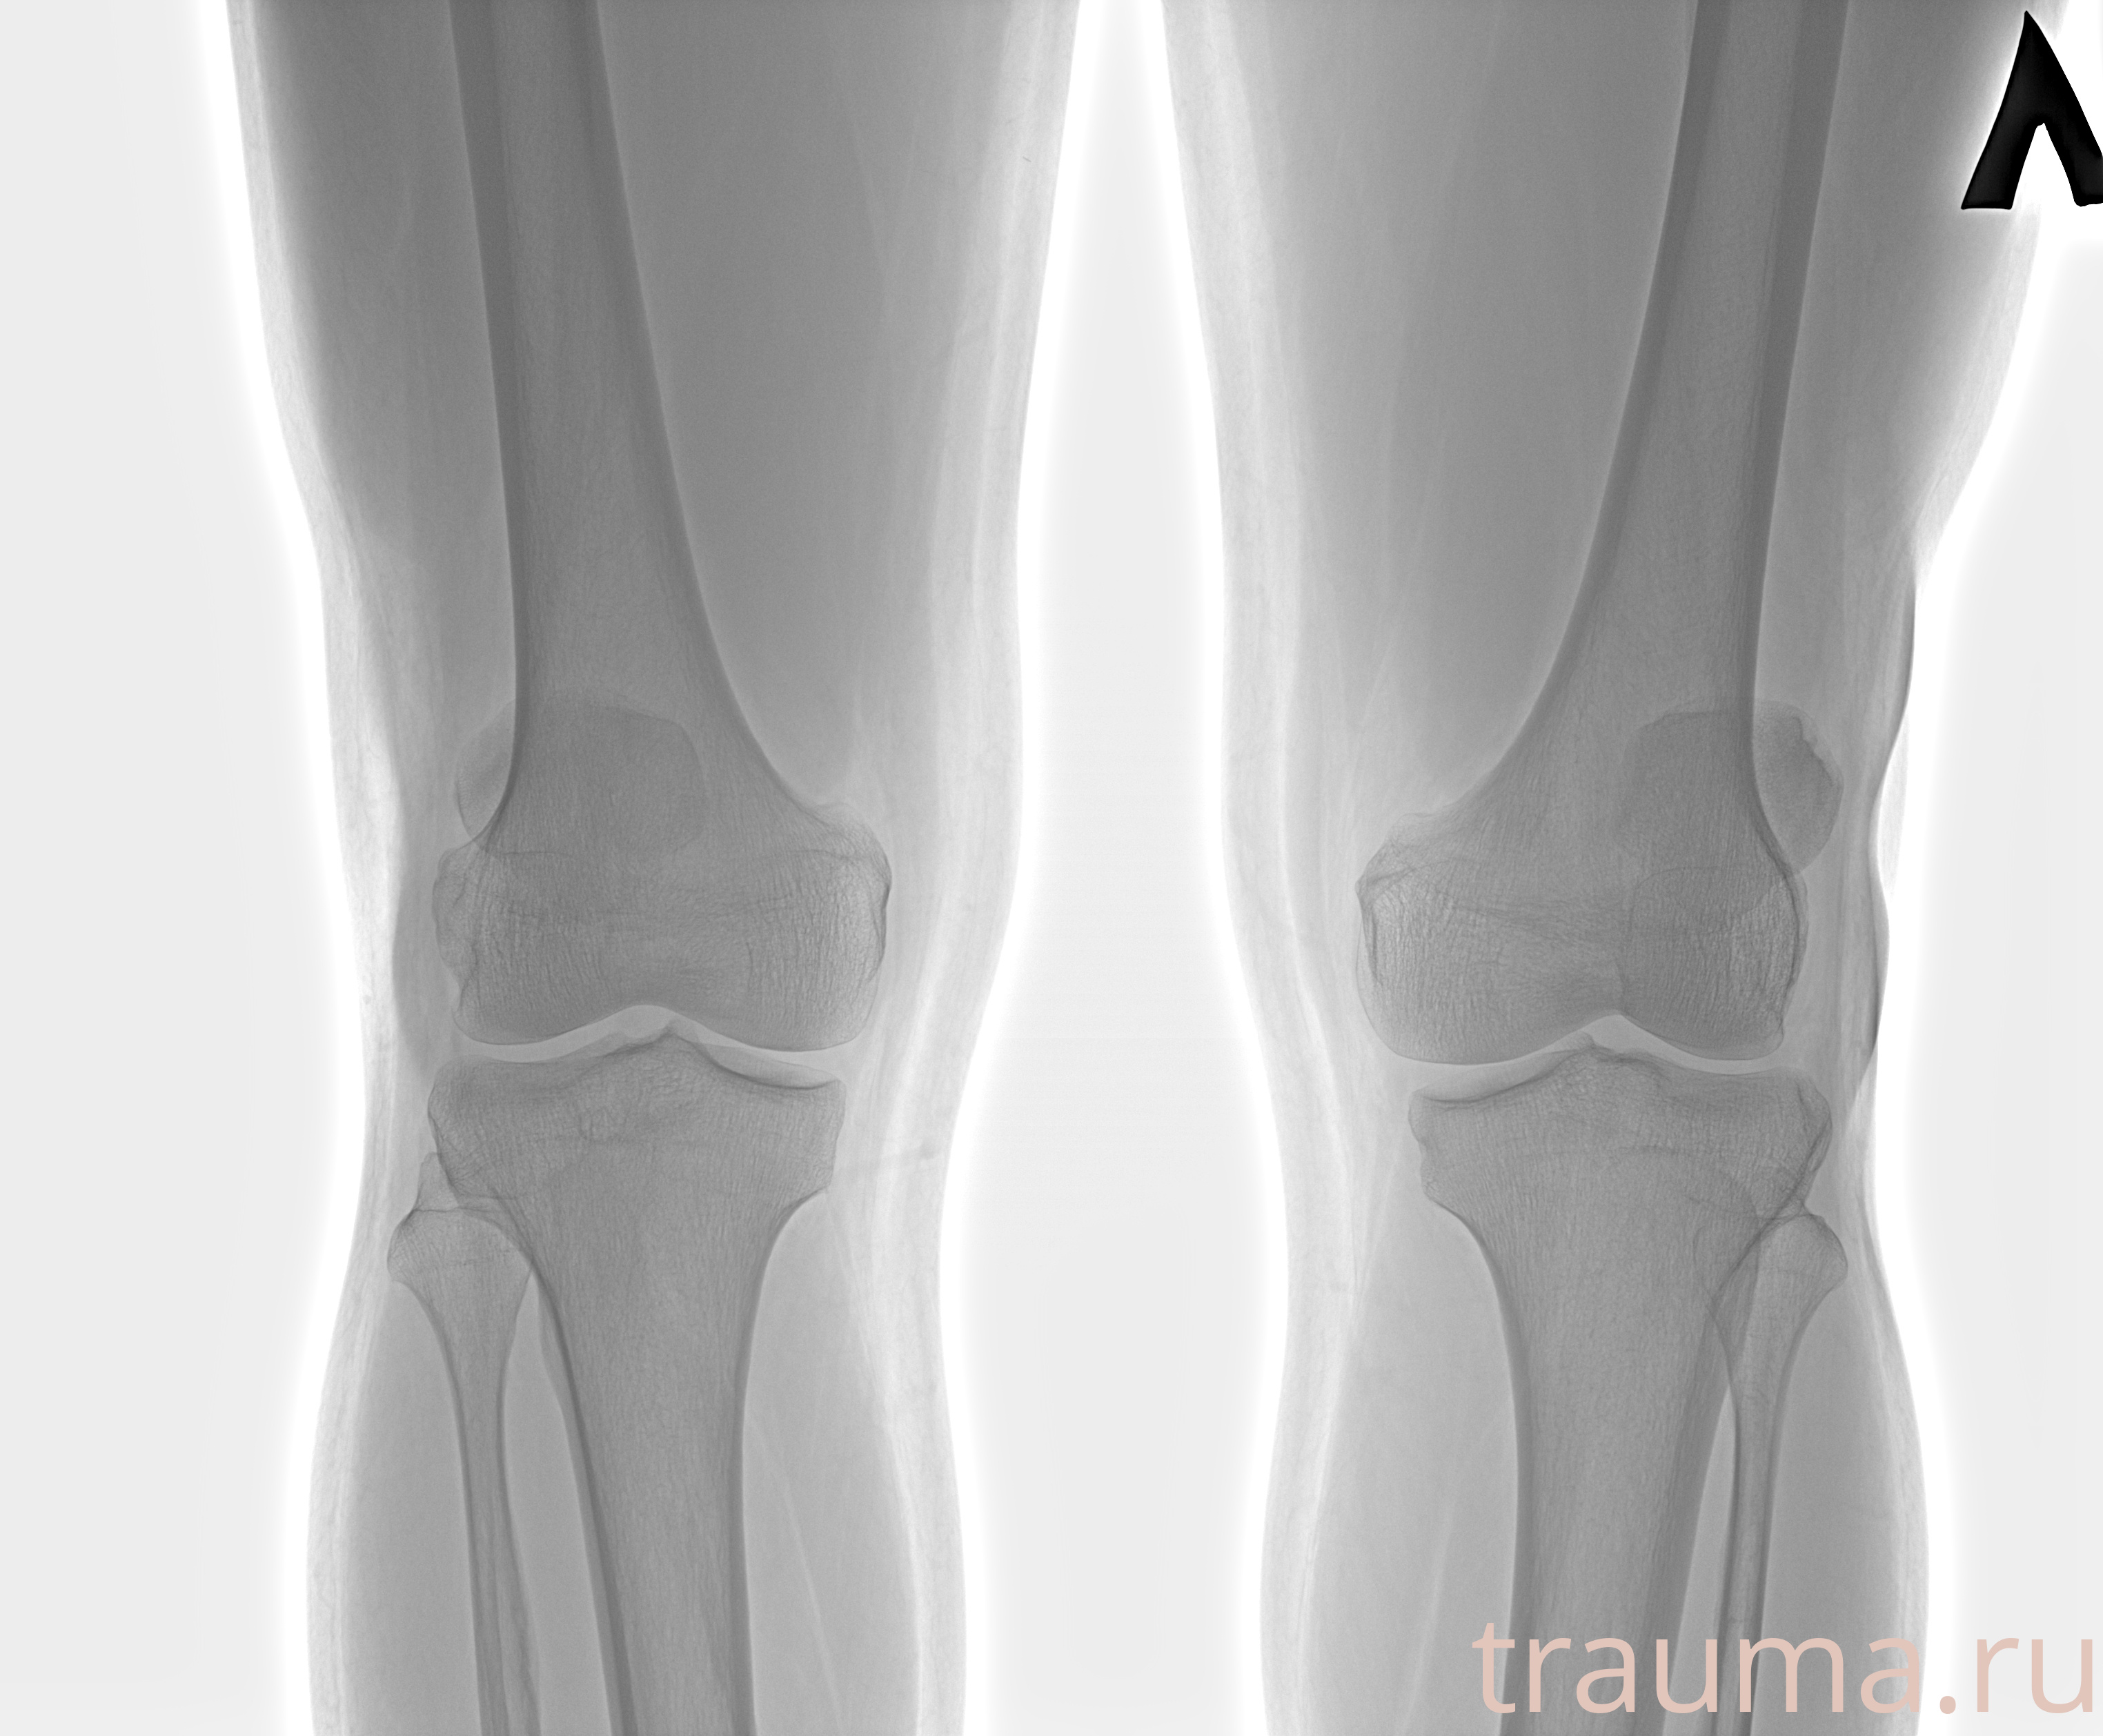

Рентген на дому: по вашему адресу приезжает врач-рентгенолог, травматолог-ортопед с мобильным рентгеновским аппаратом, проводит диагностику травмы или заболевания, делает необходимые рентгенограммы, дает рекомендации по дальнейшему лечению. Получить качественные снимки в домашних условиях возможно благодаря уникальной методике, разработанной МосРентген Центром для института  Склифосовского